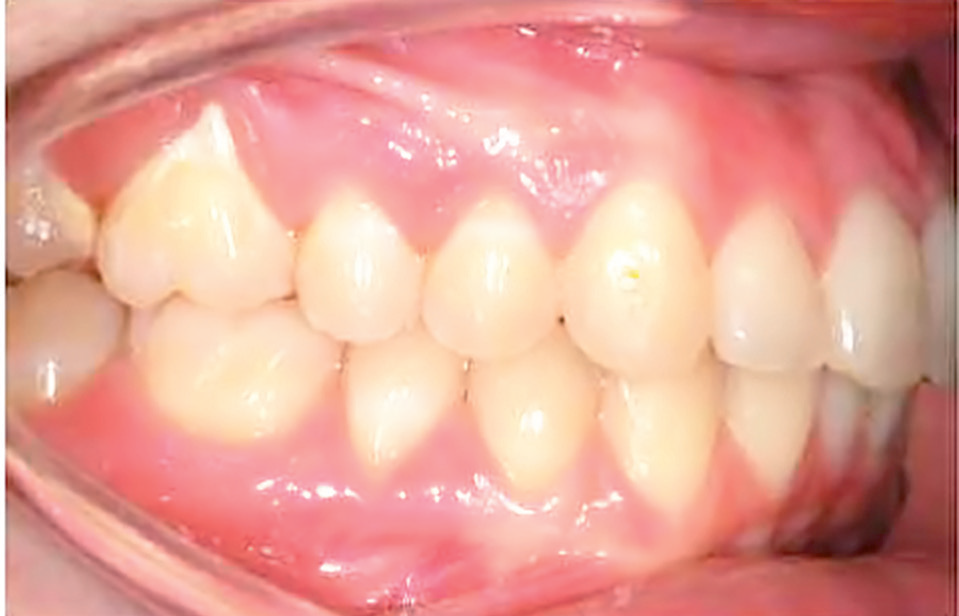

Streszczenie: Główne potrzeby, z powodu których pacjenci specjalnej troski zgłaszają się do leczenia ortodontycznego, to chęć poprawy wyglądu twarzy i uzębienia oraz interakcji społecznych. Współpraca pacjentów i ich rodziców ma decydujące znaczenie dla sukcesu leczenia. Cel publikacji: przedstawienie opisu przypadku, w którym uzyskano satysfakcjonujące wyniki leczenia – zarówno funkcjonalne, jak i estetyczne – u pacjentki z upośledzeniem umysłowym, wrodzonym oczopląsem i ciężką skoliozą. Zastosowane materiały: aparat stały Pendulum z miniimplantami jako narzędziem zakotwienia. Wyniki: poprawa estetyki twarzy i uzębienia, korekta wady zgryzu klasy II i brak resorpcji korzeni w badaniu radiologicznym. Wniosek: istotnymi czynnikami sukcesu leczenia okazały się: poznanie ograniczeń pacjentów specjalnej troski, zmotywowanie do współpracy rodziców i pacjentki, posiadanie dobrze wyszkolonego zespołu, a także dobór szybkiej i niedrogiej metody leczenia ortodontycznego.